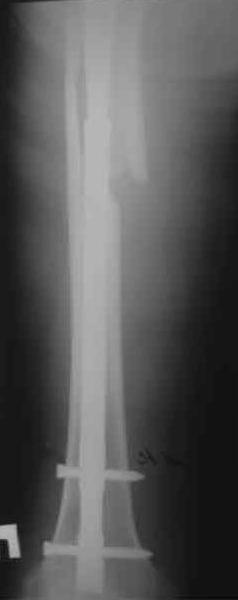

Пациенту 72 года, оперировался 11 лет назад в ГКБ15 Москва. Судя по снимку ножка споторно фирмы матис. Вряд ли сможем найти такую же для примерки.

Дополнительные снимки